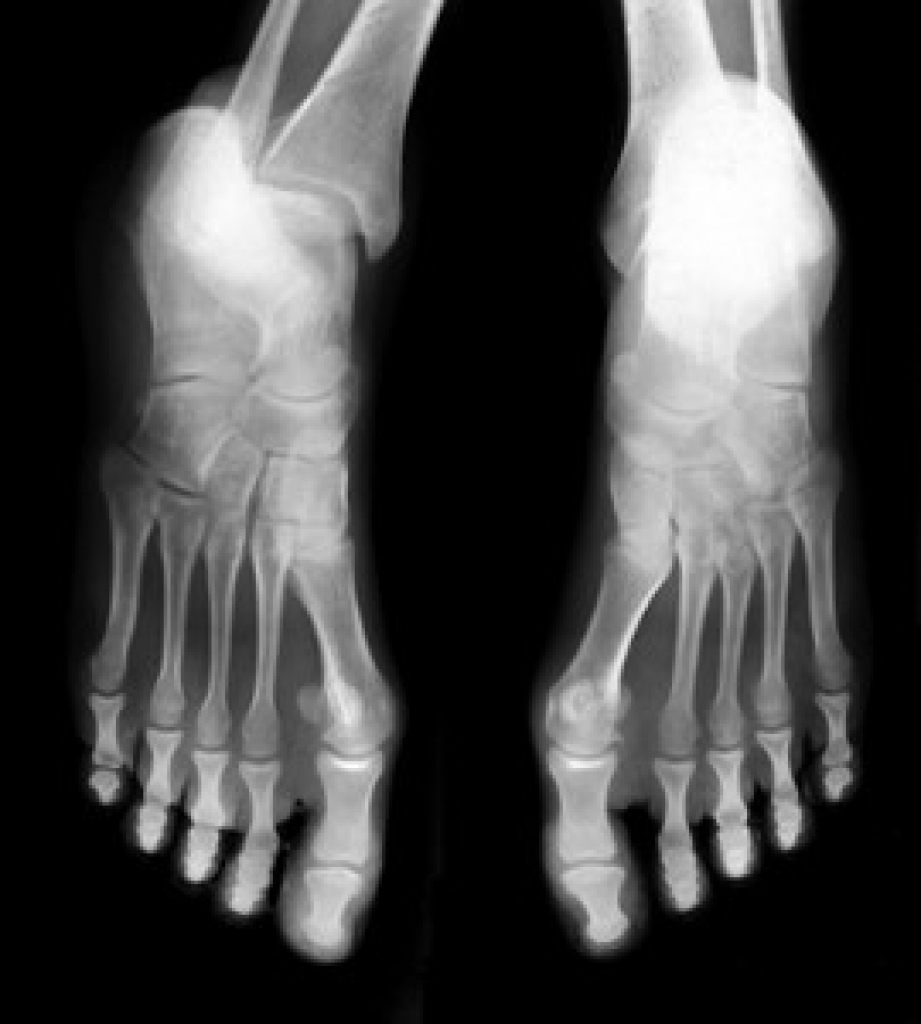

Poor Circulation in the Feet

Poor blood circulation in the feet and legs is can be caused by peripheral artery disease (PAD), which is the result of a buildup of plaque in the arteries.

Plaque buildup or atherosclerosis results from excess calcium and cholesterol in the bloodstream. This can restrict the amount of blood which can flow through the arteries. Poor blood circulation in the feet and legs are sometimes caused by inflammation in the blood vessels, known as vasculitis.